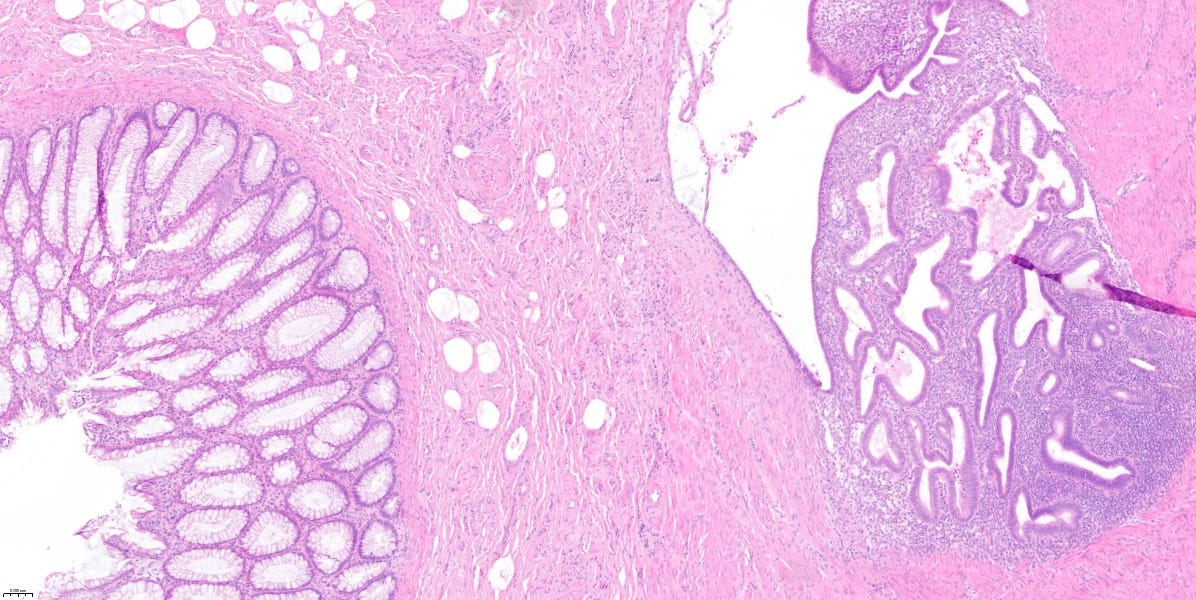

Kazuistika mesiaca

📝 Tento prípad mi „pristál” na stole počas tvorby tohto newslettera (úroveň 2/5). Karma predsa len existuje. 🙂

Resekát časti hrubého čreva 38-ročnej ženy, s mnohopočetnými suspektnými ložiskami v jej stene a pod viscerálnym peritoneom, ktoré boli viditeľné voľným okom.

✅ D. Endometrióza hrubého čreva.

💡 Endometrióza je prítomnosť „ostrovčekov” histologicky normálneho endometria v iných tkanivách a orgánoch než je výstelka (sliznica) dutiny maternice.

V ektopických lokalitách podliehajú endometriálne žliazky a stróma rovnako hormonálnym zmenám ako v dutine maternice.

V dôsledku toho vznikajú ložiská krvácania, ktoré sa postupne organizujú, neskôr peritoneálne zrasty v prípade GIT-u, atď. Klinický obraz je preto rôznorodý, v závislosti od lokality postihnutého tkaniva.